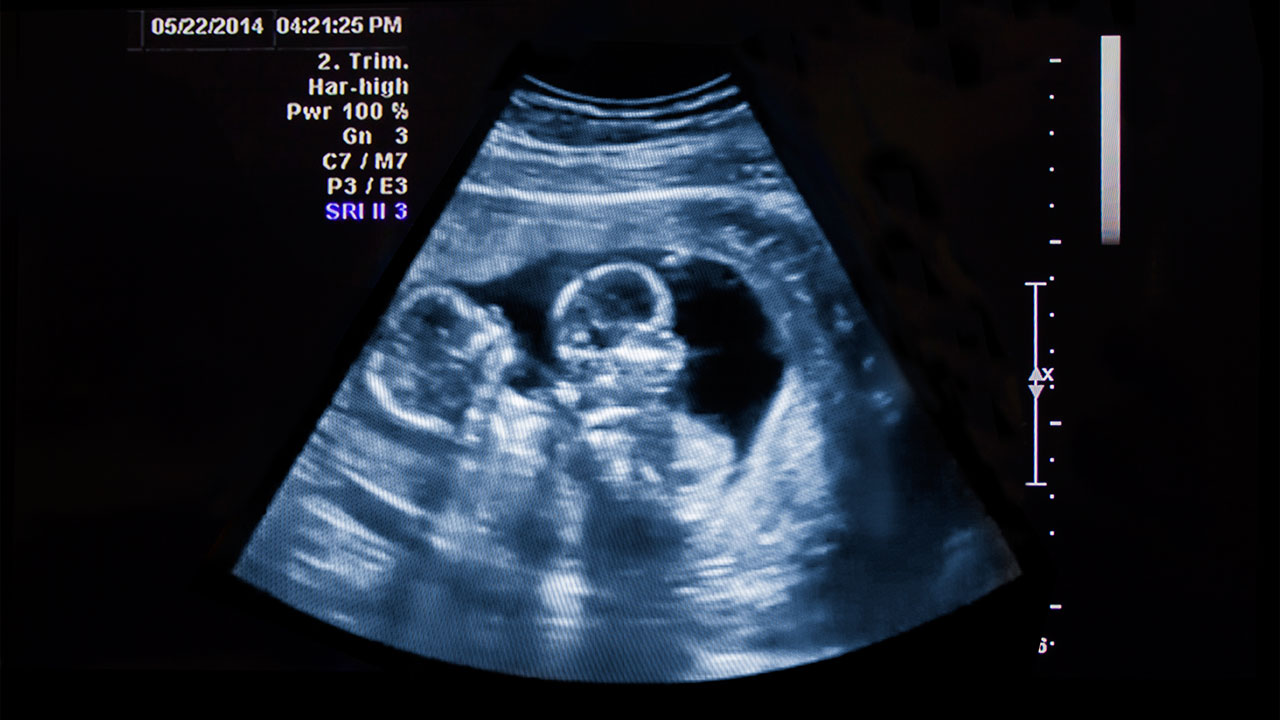

जुम्ल्याहा बच्चाको चाहाना हरेक दम्पतीलाई हुन थालेको छ । तर वास्तवमा जुम्ल्याहा सन्तान गर्भमा आउनु, जुम्ल्याहा बच्चा जन्माउनु भनेको निकै रिस्क कुरा रहेको प्रजनन रोग विशेषज्ञहरू बताउँछन् ।

एउटा गर्भाशयमा दुई वटा गर्भको तुलनामा एउटै बच्चा हुर्काउने प्रक्रिया सहज हुन्छ,। दुई वटा गर्भ रहनु भनेको गर्भावस्थाको समस्या दोब्बर हुनु हो । एउटा गर्भ रहँदा जति समस्या हुन्छ, दुई वटा गर्भ रहँदा त्यो भन्दा दोब्बर हुन्छ ।

गर्भाशयमा दुई वटा भ्रूणले बढी ठाउँ ओगट्ने हुँदा पेटको आकार पनि तुलनात्मक रूपमा बढ्छ । पेटको आकार सामान्य भन्दा ठूलो हुँदा बच्चा चाँडै जन्मने गर्छ ।

जस्तो अरू ३७ हप्तामा जन्मन्छन् भने जुम्ल्याहा बच्चा त्यसअघि नै जन्मन्छन् । अर्थात् उमेर नपुग्दै बच्चा जन्मन्छन् । यसैगरी पाठेघर खुम्चिन ढिलो हुने हुँदा रक्तस्राव बढी हुन्छ । आमालाई मधुमेह, उच्च रक्तचाप जस्ता समस्या थपिने जोखिम हुन्छ । अर्को जोखिम भनेको कतिपय अवस्थामा दुई बच्चाको शरीर जोडिएर जन्मिन सक्छन् ।